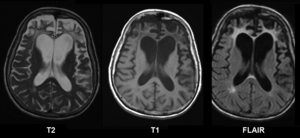

Brain MRI in Pick's disease